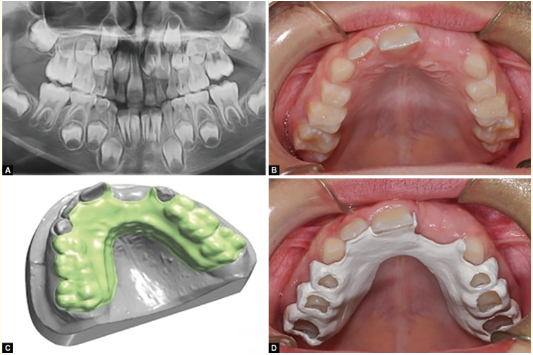

Khyati Arora, Lakshbir Singh, Navneet Kaur and Gurpreet Kaur. 21(12): 29-39.

Aylin Pasaoglu Bozkurt. 21(12): 50-58.